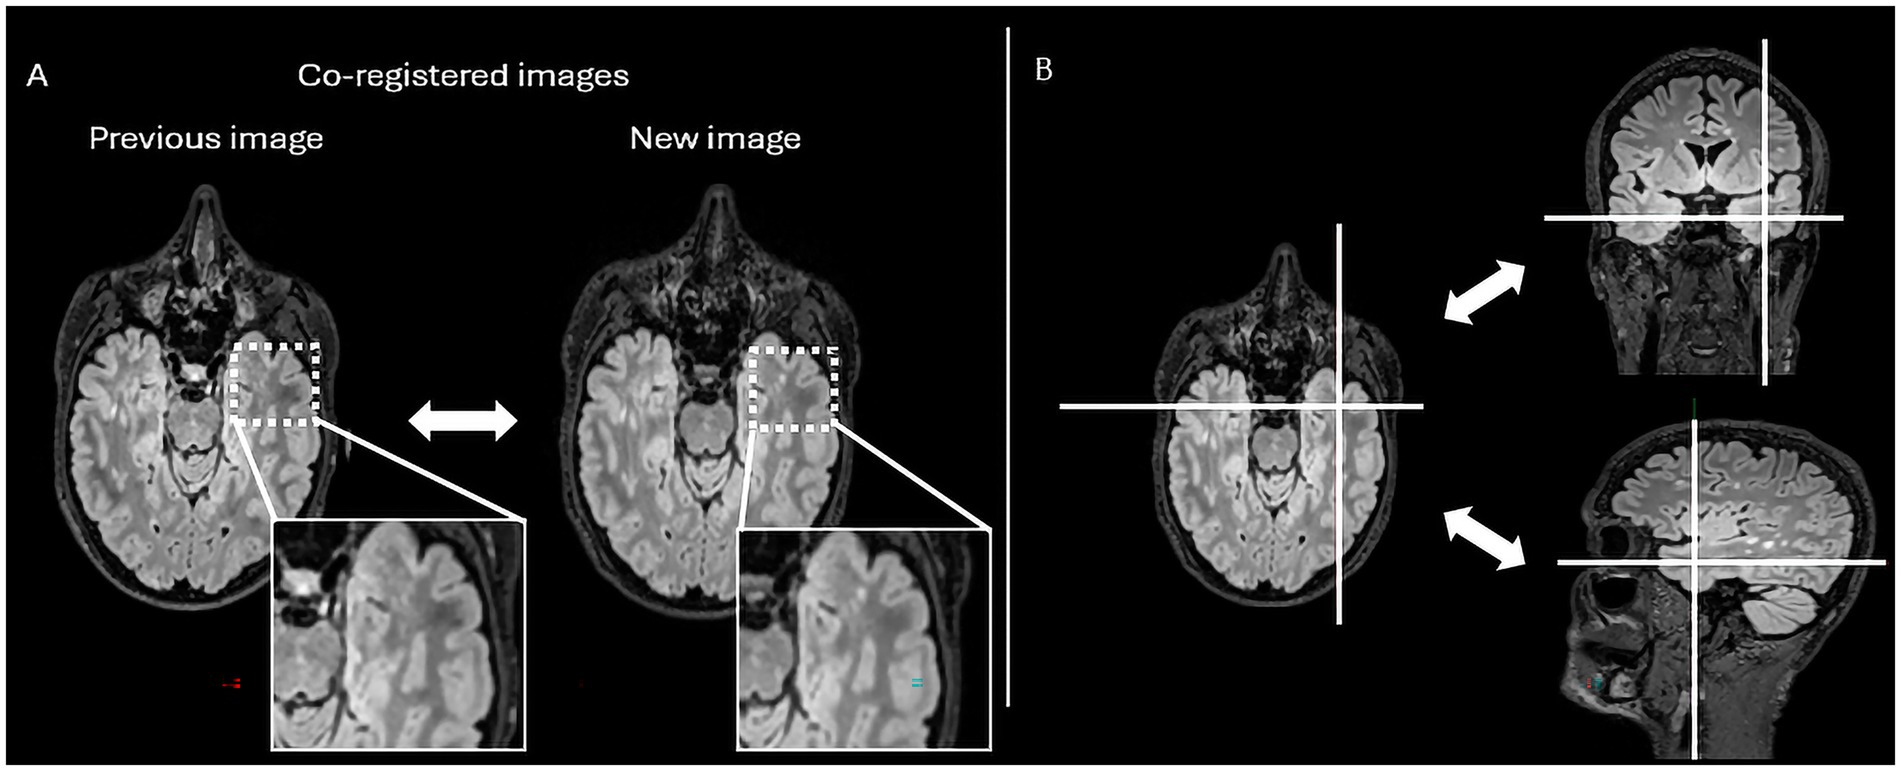

In practical terms, Jazz® enables radiologists to directly compare prior and follow-up scans at the same anatomical location, allowing instantaneous toggling between time points with a single click (mouse or keyboard shortcut). This synchronized display helps the reader identify subtle signal changes. In addition, the software provides a “lesion locking” option: once a lesion is selected, the tool automatically tracks its anatomical location across different time points, ensuring consistent assessment of potential lesion evolution (Figure 1).

Figure 1. The figure represents the reading interface in Jazz® software. It allows a comparison of previous and new MRI FLAIR images of a patient with MS. The reader can easily switch from previous to new image, and vice versa, just by mouse clicking or using a keyboard shortcut (A), while there is as well lesion locking option (B) when the software automatically detects lesion’s anatomical location.